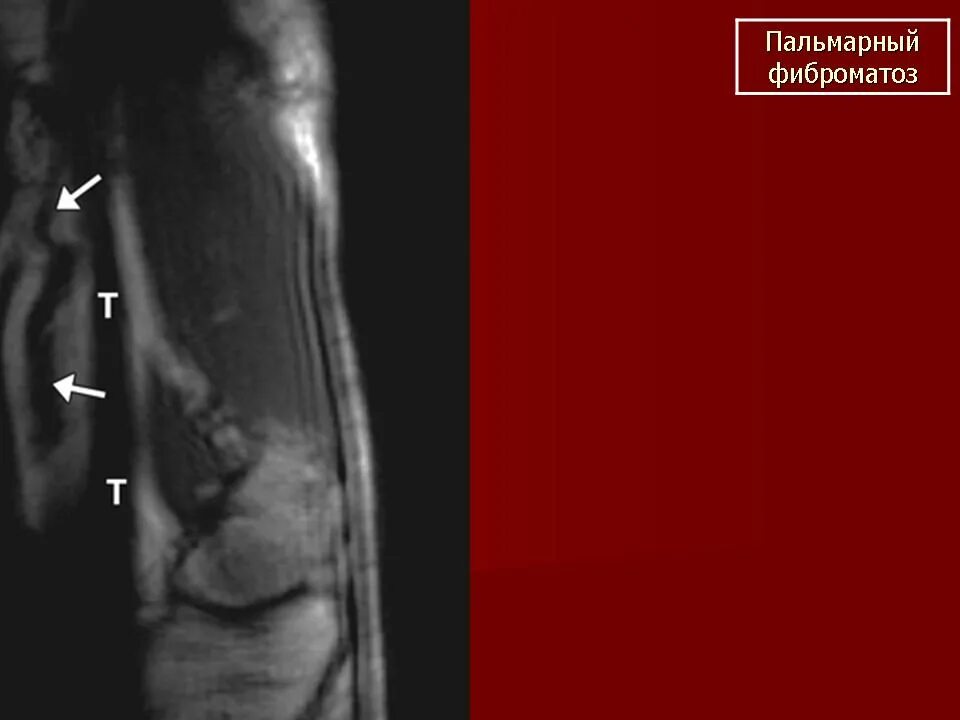

Фиброматоз мягких